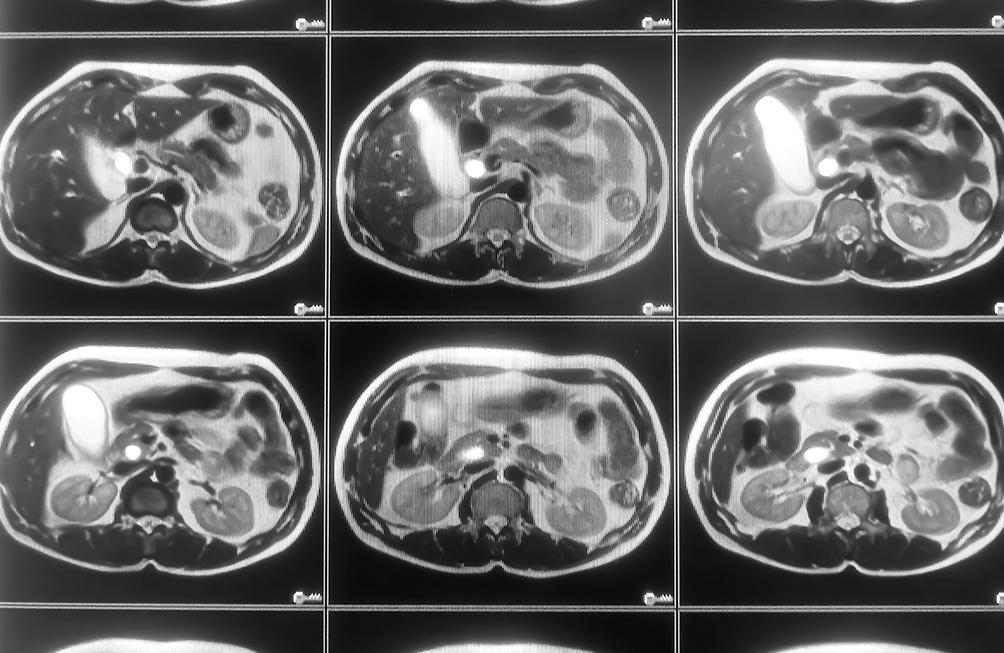

L'IRM rénale est une technique non invasive, qui permet d’évaluer la santé et la structure des reins. Elle est généralement demandée pour :

- Diagnostic de tumeurs ou masses : Pour détecter et caractériser des tumeurs rénales, qu’elles soient bénignes ou malignes.

- Recherche d’obstructions ou calculs : Pour visualiser des calculs rénaux ou des obstructions dans les voies urinaires.

- Vérification de la vascularisation : Pour étudier la circulation sanguine dans les reins, notamment en cas de suspicion d’atteinte vasculaire.